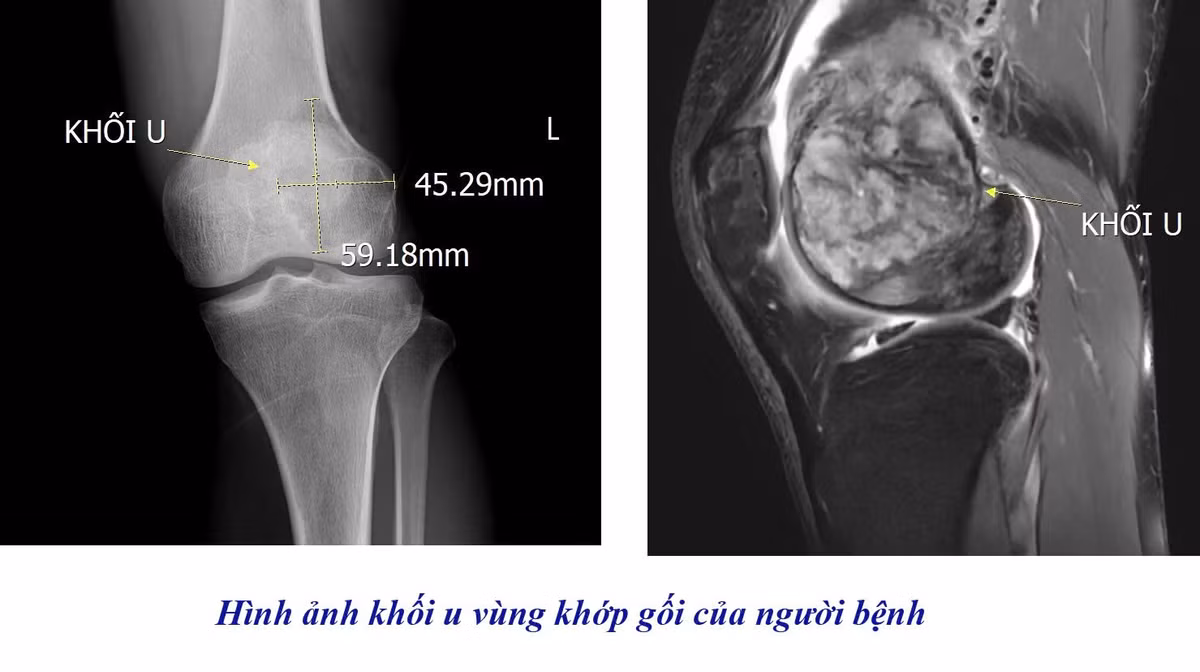

Qua thăm khám lâm sàng và chỉ định chẩn đoán hình ảnh, các bác sĩ đã tiến hành chụp cộng hưởng từ (MRI) khớp gối. Kết quả cho thấy người bệnh có khối u tế bào khổng lồ tại vùng khớp, cần được theo dõi và điều trị chuyên sâu nhằm tránh các biến chứng nguy hiểm.

U tế bào khổng lồ phát triển trong khớp gối bệnh nhân - Ảnh BVCC